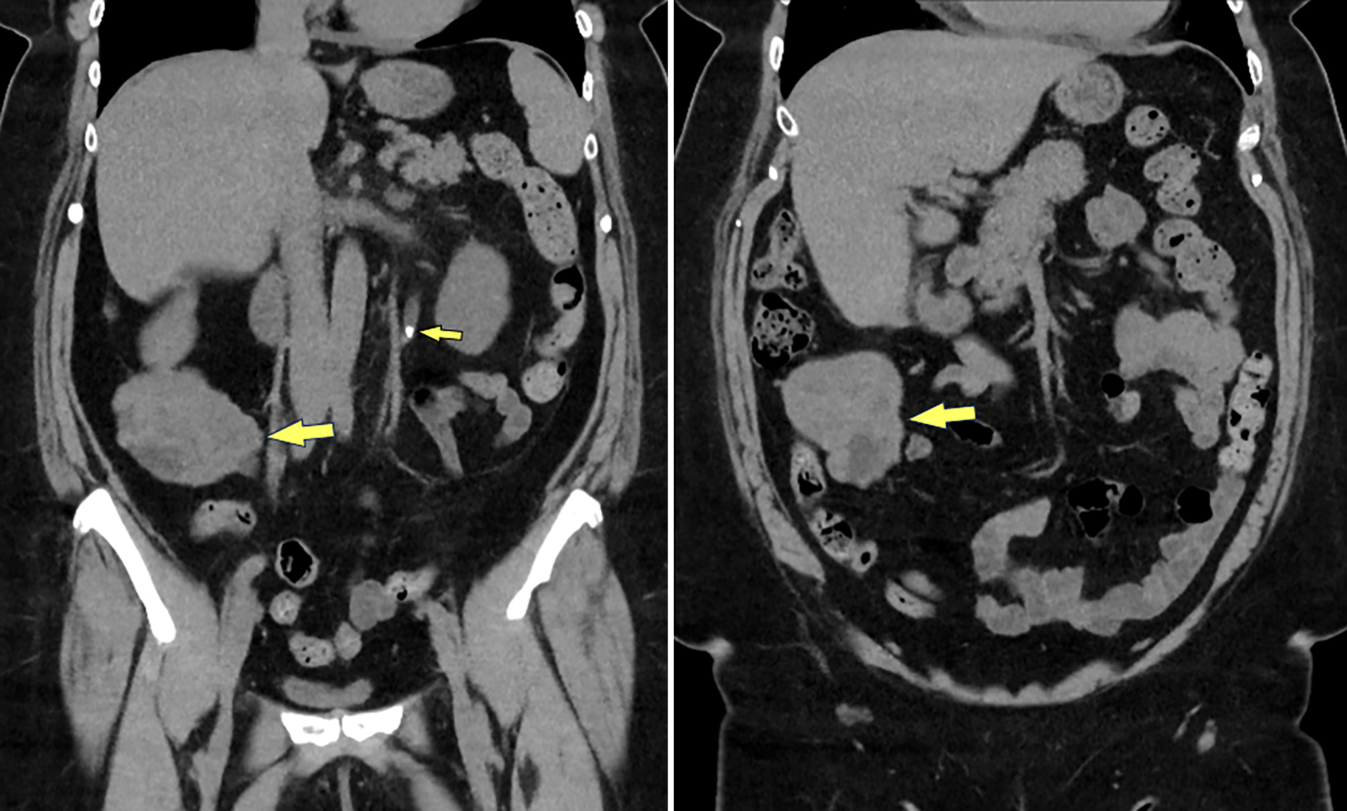

Abb. 1

Die Nativ-MDCT von Niere und ableitenden Harnwegen zeigt das proximale Ureterkonkrement links (kleiner Pfeil) und den Zufallsbefund einer Raumforderung im rechten Mittelbauch (große Pfeile), mit Nahebeziehung zu Darmschlingen